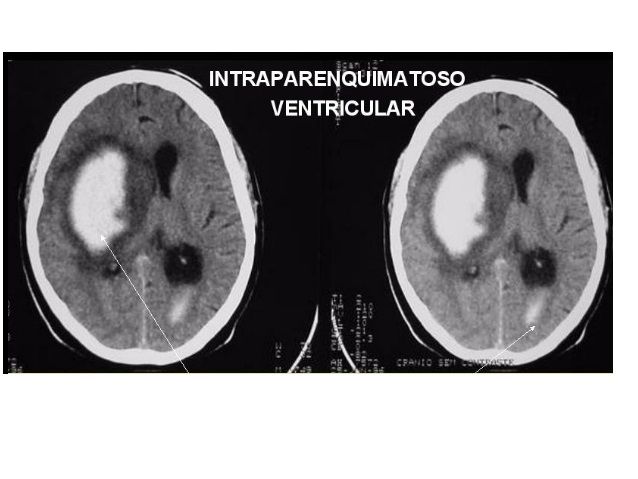

1. INTRACEREBRAL

2. DIAGNÓSTICO: EXAMES DE NEUROIMAGEM (TC OU RNM), IDENTIFICAR LOCAL E TAMANHO DA HEMORRAGIA